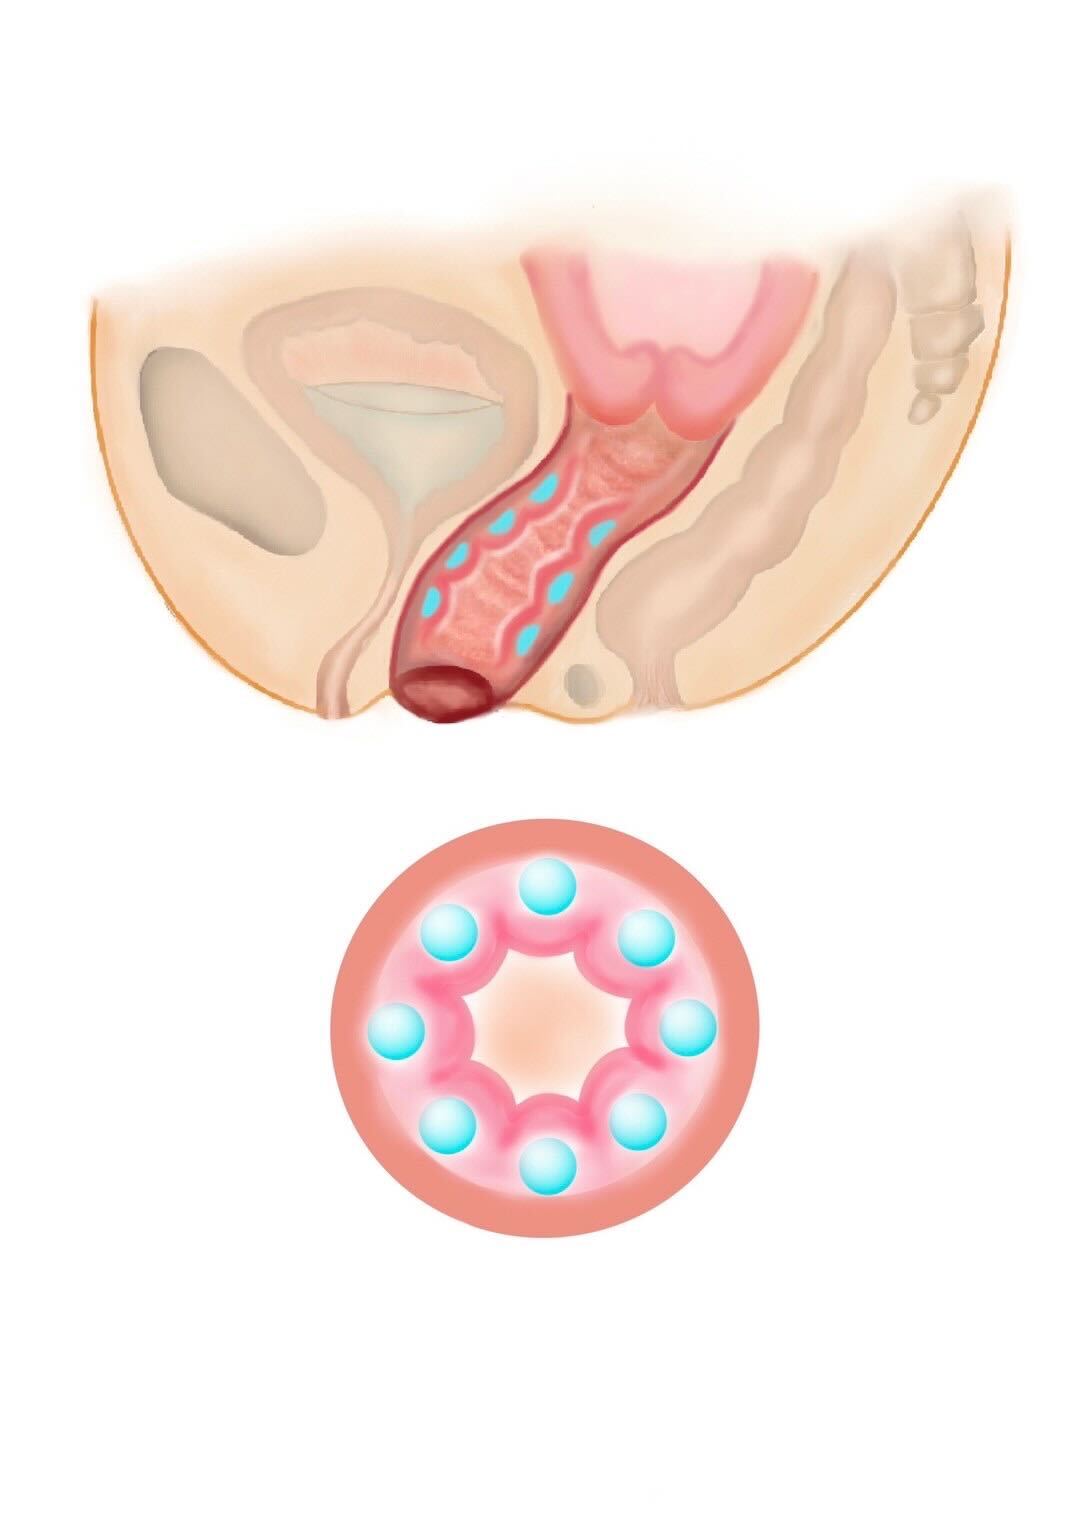

Type03

きんちゃく

② 円周注入(膣の締まり感向上)

膣の周囲に均等に注入し、膣壁にボリュームをもたせる方法で、膣粘膜のハリを高め、膣のフィット感を向上させる可能性があります。

出産後に膣のゆるみを感じる方、膣のハリ不足が気になる方に適しています。

また、ご希望に応じて、巾着、タコつぼ、数の子天井、俵締め、みみず千匹などと称される施術方法にも対応しております。